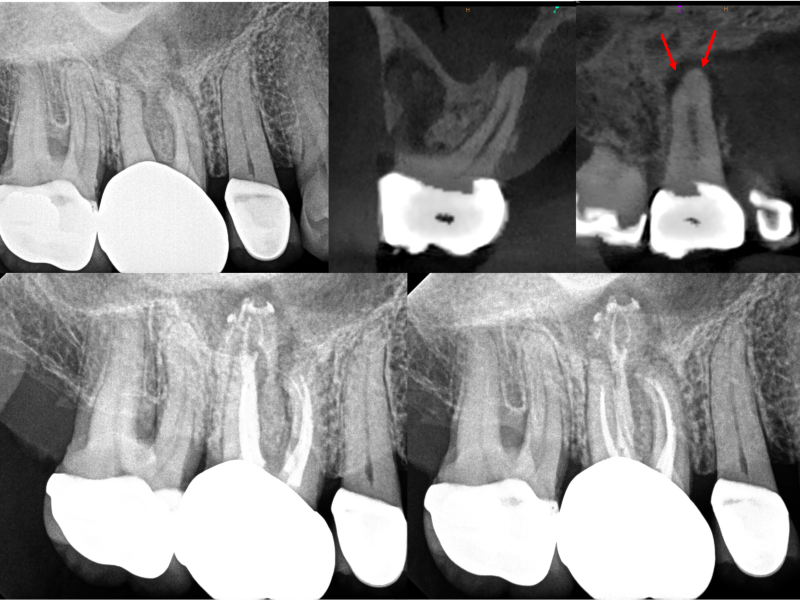

Middle Mesials in MN Molars

Karen S. Potter, DDS

View Case Images